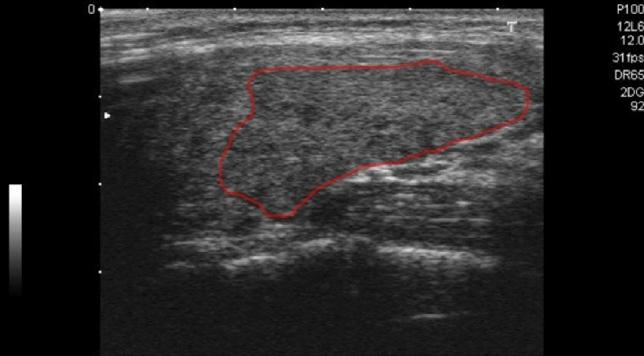

一种基于深度学习的甲状腺结节超声图像分类 CADx 架构。

A Novel Deep-Learning-Based CADx Architecture for Classification of Thyroid Nodules Using Ultrasound Images.

Nodules of thyroid cancer occur in the cells of the thyroid as benign or malign types. Thyroid sonographic images are mostly used for diagnosis of thyroid cancer. The aim of this study is to introduce a computer-aided diagnosis system that can classify the thyroid nodules with high accuracy using the data gathered from ultrasound images. Acquisition and labeling of sub-images were performed by a specialist physician. Then the number of these sub-images were increased using data augmentation methods. Deep features were obtained from the images using a pre-trained deep neural network. The dimensions of the features were reduced and features were improved. The improved features were combined with morphological and texture features. This feature group was rated by a value called similarity coefficient value which was obtained from a similarity coefficient generator module. The nodules were classified as benign or malignant using a multi-layer deep neural network with a pre-weighting layer designed with a novel approach. In this study, a novel multi-layer computer-aided diagnosis system was proposed for thyroid cancer detection. In the first layer of the system, a novel feature extraction method based on the class similarity of images was developed. In the second layer, a novel pre-weighting layer was proposed by modifying the genetic algorithm. The proposed system showed superior performance in different metrics compared to the literature.

甲状腺癌结节在甲状腺细胞中呈现良性或恶性类型。甲状腺超声图像主要用于甲状腺癌的诊断。本研究的目的是引入一种计算机辅助诊断系统,该系统可以使用从超声图像中收集的数据对甲状腺结节进行高精度分类。通过专家医生对亚图像进行采集和标注。然后,使用数据增强方法增加这些子图像的数量。使用预先训练的深度神经网络从图像中提取深度特征。减少特征的维度并改进特征。将改进后的特征与形态学和纹理特征相结合。使用相似系数生成模块获得的相似系数值来对该特征组进行评分。使用带有新颖设计的预加权层的多层深度神经网络对结节进行良性或恶性分类。在这项研究中,提出了一种用于甲状腺癌检测的新型多层计算机辅助诊断系统。在系统的第一层,开发了一种基于图像类相似性的新型特征提取方法。在第二层,通过修改遗传算法提出了一种新的预加权层。与文献相比,所提出的系统在不同指标下表现出优异的性能。